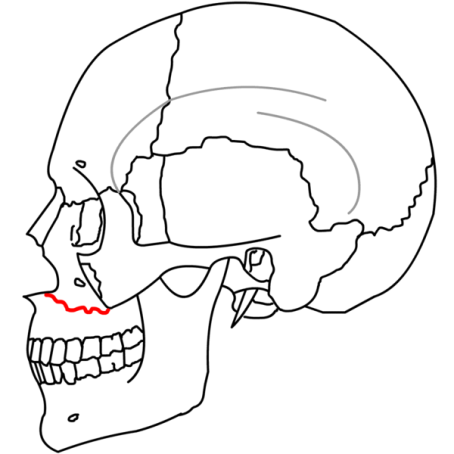

| Lefort I - Maxilla completely separately from the face - fracture goes thru the lateral pyriform rim, thru maxillary sinus wall, through tuberosity, and thru the pterygoid plates | |

![]() |